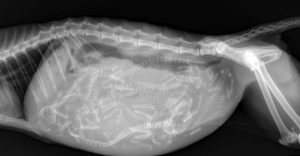

На рентгене хорошо просматриваются кости и позвоночник. Шерсть уже полностью сформирована. В целом на 50-й день котята уже готовы к рождению, но данный момент также зависит от породы.